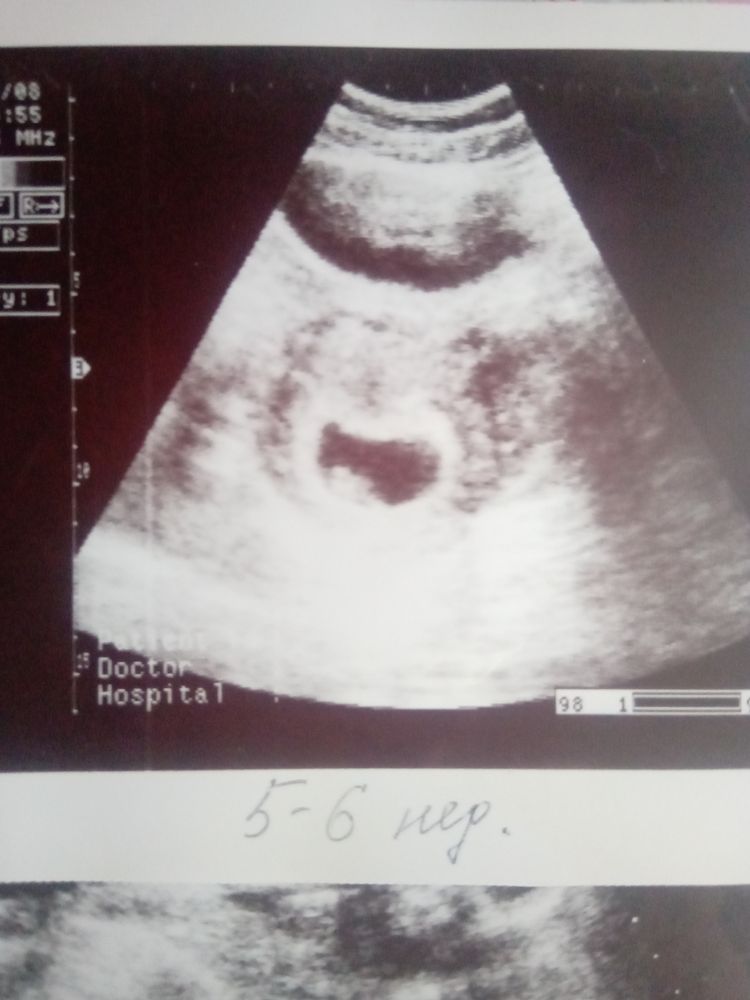

Вторая дочка, узи 16 лет назад)) срок 5-6 недель поставили. Эмбрион, сб+ Изображение